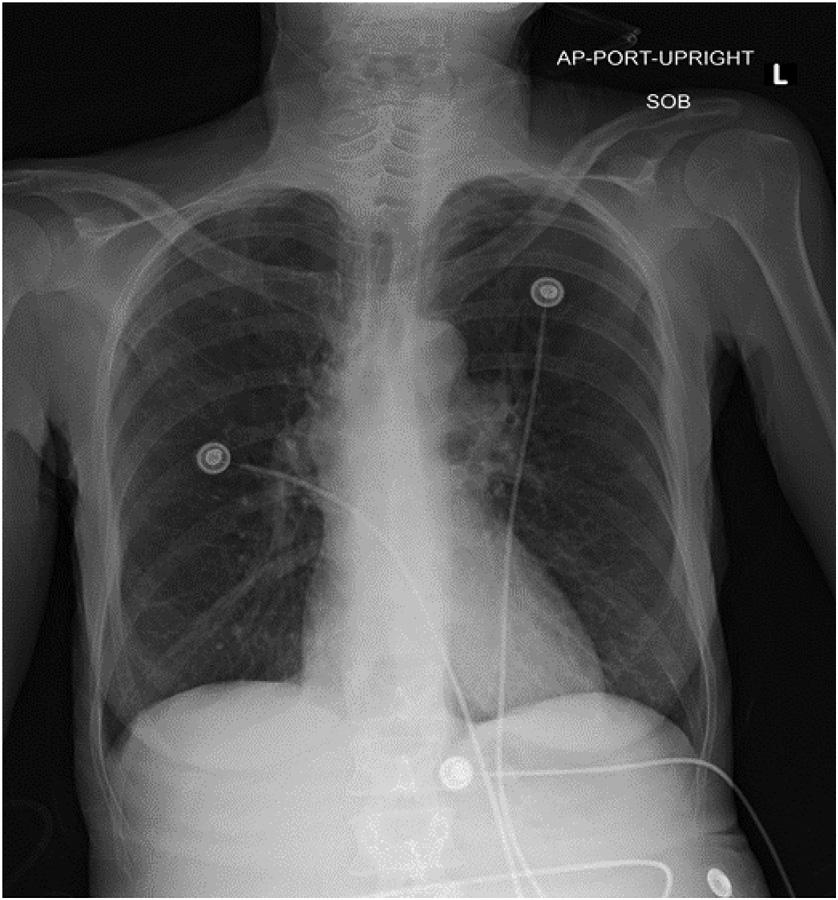

elevatedbloodureanitrogen(BUN)andcreatinine.Liver functiontestswerenotableforanelevatedaspartate aminotransferase(AST)withanormalalanine aminotransferase(ALT)levelalongwithanelevatedalkaline phosphatasewithnormaltotalbilirubin.Urinalysiswas notableforpyuria,hematuria,andleukocyteesterase.Initial lactatewas3.8millimolesperliter(mmol/L),whichtrended downto3.1mmol/Laftercrystalloidandvasopressor therapyinitiation.Troponinbiomarkerwaselevatedalong withNT-pro-B-natriureticpeptideandD-dimer.An electrocardiogram(ECG)andachestradiograph(CXR) wereobtainedaswell(Images1 and 2).

HerCXRisgenerallyunremarkable,withouttheclassic (althoughuncommon) findingsassociatedwithPEsuchas Hamptonhump,Westermarksign,parenchymal consolidation,Fleischnersign,orpleuraleffusion.1 Theclear CXReliminatesalargehydro/pneumothoraxora flailchest astheetiologyofhersymptoms.HerECGdemonstratesa normalsinusrhythm,withnormalintervals,normalaxis, andanisolatedT-waveinversioninleadaVL,eliminating acutecoronarysyndromeasthecauseofher chestpain.

Achestradiograph(CXR)(Image1)showedalargehiatal herniawithtracebilateralpleuraleffusionsanddisplacement ofthegastricbubbletotheright.Computedtomography (CT)withcontrastofthechest/abdomen/pelvis(Images2 and 3)demonstratedalargehiatalherniawithmostofthe stomachinthechest,associatedvolvulus,bilateralpleural effusions,rightgreaterthanleft,andacomplex,partially fluid-filledcollectionalongtheposterioraspectofthehiatal

Anterior-posteriorchestradiographdemonstratinglarge hiatalherniawithdisplacementofthegastricbubble(arrow)from lefttoright.